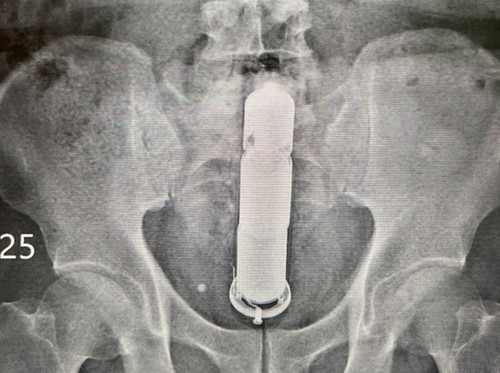

Theo bác sĩ phẫu thuật Trần Vinh Kiên, cách đây vài ngày, anh đã phẫu thuật cho một người đàn ông đến bệnh viện cấp cứu vào nửa đêm. Chụp X-quang cho thấy có dị vật dài 30cm trong ruột.

| Hình ảnh phim X-quang do bác sĩ Trần cung cấp. |